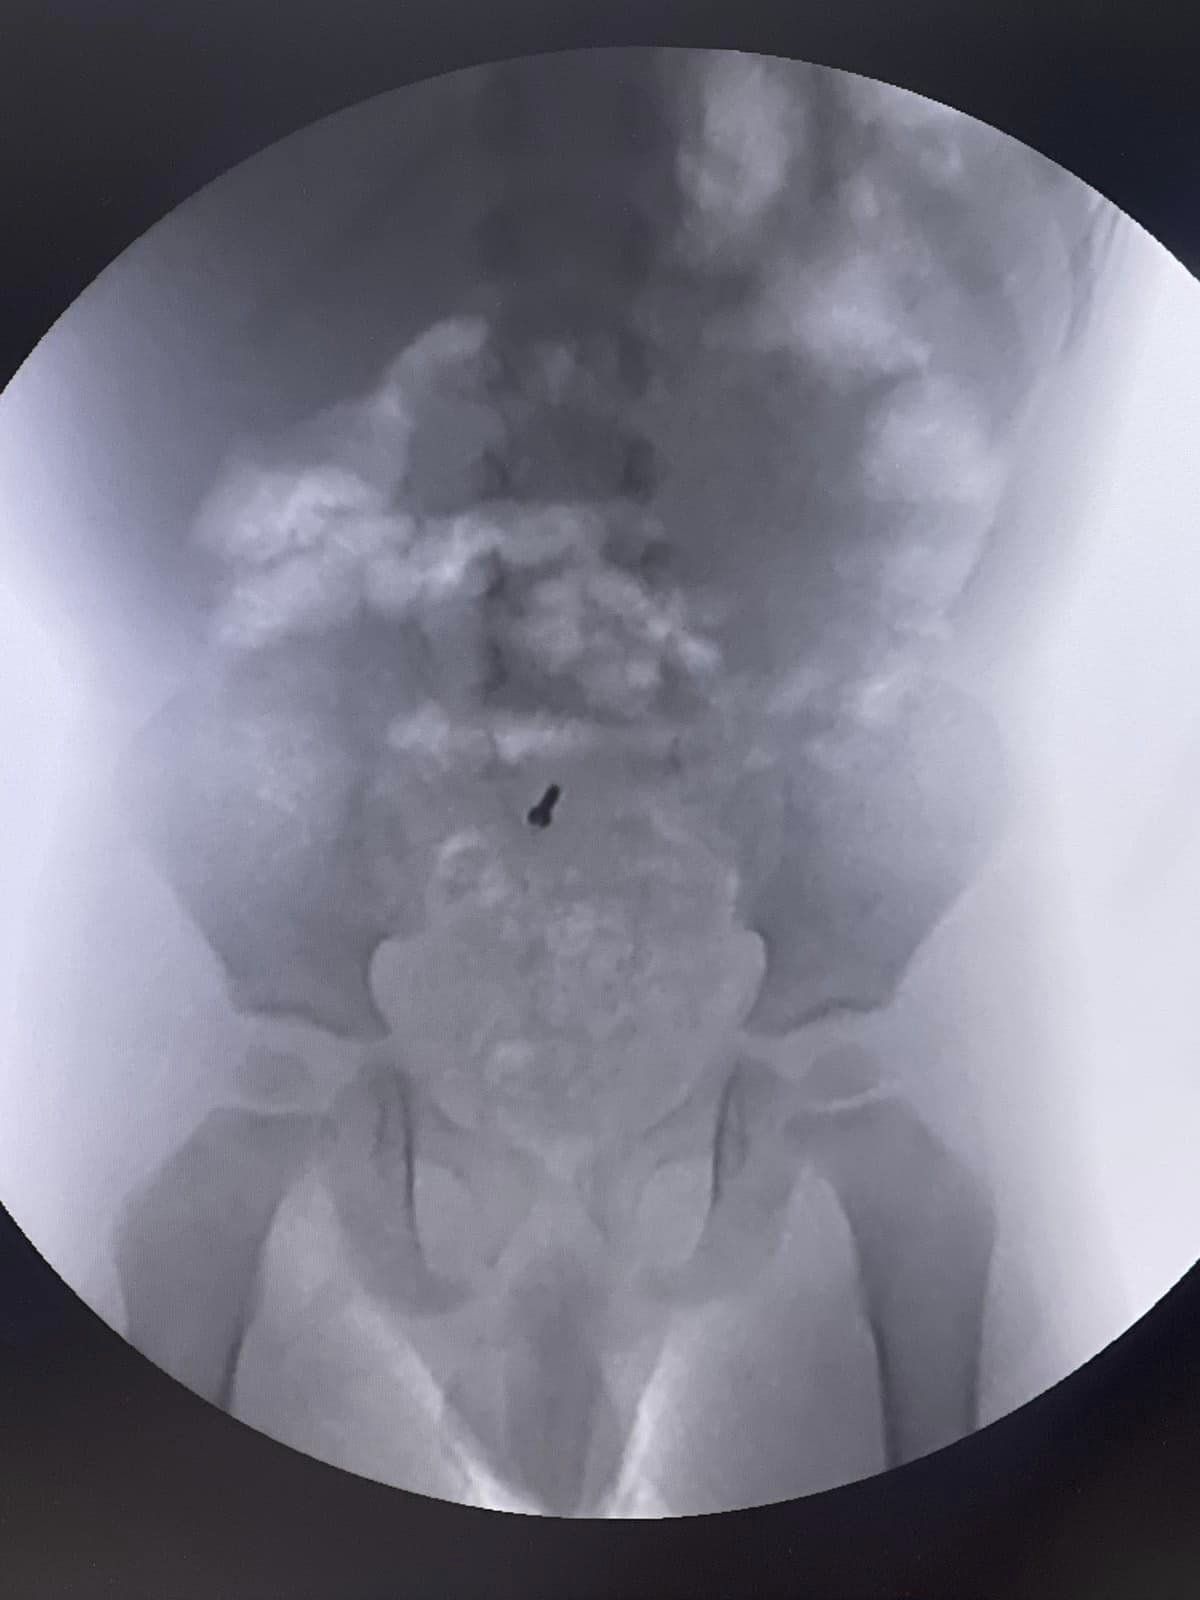

Данилку нещодавно виповнилося три рочки. У вересня, по стану здоров’я, йому потрібно було зробити рентгенографію і, під час діагностичного дослідження, лікарі випадково виявили металевий шуруп у його черевній порожнині.

Медики разом із батьками вирішили спостерігати і сподівалися, що шурупчик вийде самостійно. При повторних рентгенах, шуруп, на жаль, залишався на місці.

Батьки вирішили звернутися до львівської обласної дитячої лікарні Охматдит. При обстеженні дитини, лікар-ендоскопіст Марта Лучак провела колоноскопію, проте шуруп не виявили.

Тоді хірурги вирішили провести діагностичну лапароскопію, перевірили весь кишківник і знайшли шуруп в апендиксі, що буває вкрай рідко. Після знахідки одразу видалили його.